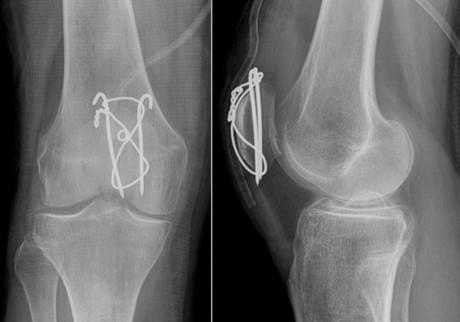

Удаление спиц и проволоки после остеосинтеза надколенника по Веберу

При переломах надколенника (коленной чашечки) со смещением отломков выполняется операция остеосинтеза, т.е. скрепление костных фрагментов для восстановления целостности кости и соответственно функции коленного сустава. Так как при отказе от операции пациент рискует остаться инвалидом.

Для остеосинтеза надколенника в подавляющем большинстве случаев используется методика Вебера. Когда костные отломки скрепляются двумя титановыми спицами Киршнера и дополнительно стягиваются титановой проволокой 8 образно. Это позволяет быстро и очень эффективно восстановить поврежденную кость и что немаловажно металлоконструкция минимальна по стоимости. Но у нее есть один большой минус. Очень часто пациенты испытывают дискомфорт и боль в области мпиц и проволоки, так как она находится правктичекски сразу под кожей. Поэтому часто выполняется удаление металлоконструкции из надколенника.

После того как кость срослась и металлоконструкция выполнила свою функцию ее можно удалить. Полное сращение кости происходит за 6- 8 месяцев, в некоторых случая 1 год. Именно спустя этот срок можно удалять металл.

Операция зачастую выполняется в условиях дневного стационара, т.е. через несколько часов после операции пациент может уйти домой. Анестезия местная, проводниковая либо наркоз. Непосредственно сама операция по времени занимает 30 минут. Найти проволку и спицы, как правило, не представляет труда для хирурга. После того как металлоконструкция удалена проводится зашивание раны и наложение асептической повязки. Пациент приходит на перевязки в первые сутки, далее можно перевязываться самостоятельно либо в лечебном учреждении рядом с домом. Швы необходимо снять через 14 дней после операции. В раннем послеоперационном периоде назначаются обезболивающие и антибактериальные препараты.

Примерно через 1 месяц после операции по удалению металлоконструкции из надколенника можно постепенно увеличивать нагрузку и возвращаться в свой обычный ритм жизни.